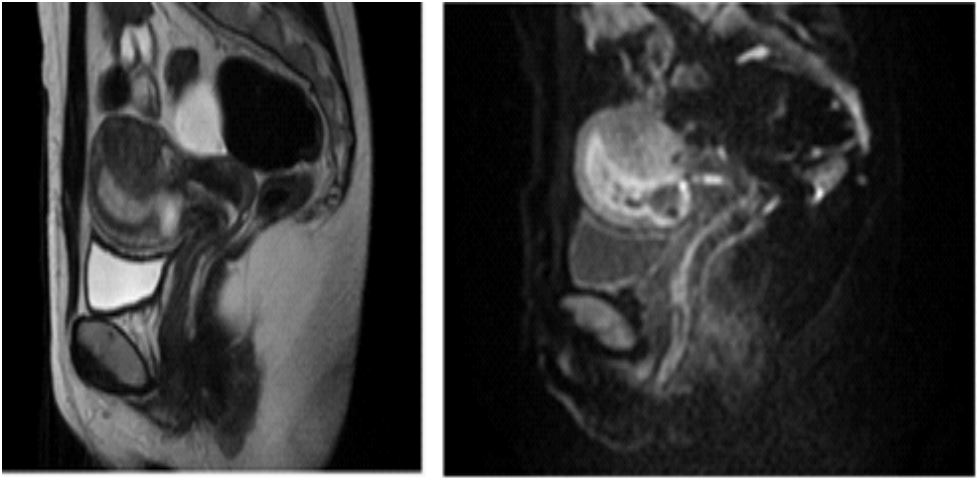

The images of pelvis Magnetic Resonance Imaging (MRI) performed during the hospital stay, confirmed the presence of a gestational sac with a diameter of 25 mm, embedded in the anterior lower uterine wall, in close contact with the perimetrium (Figures 1 and 2).

Figure 1 and 2: Pelvic Magnetic Resonance Imaging (MRI) performed before the procedure confirming the presence of a gestational sac with a diameter of 25 mm, embedded in the anterior lower uterus in close contact with the perimetrium.